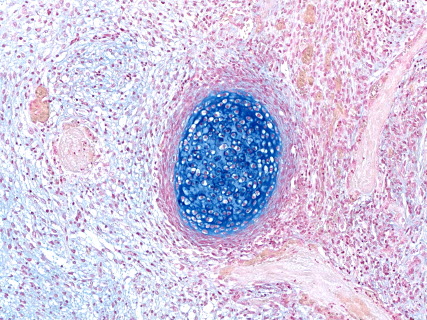

抗HLA染色(免疫染色)

(ゼノグラフト)